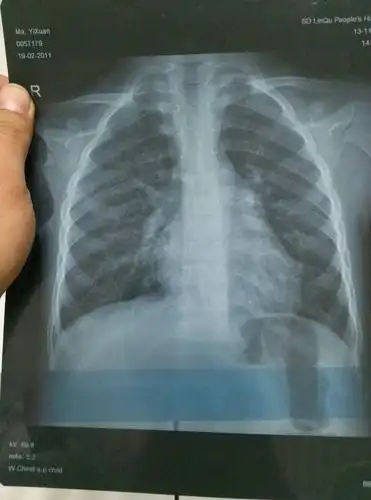

小孩四岁发烧不退诊断为肺炎,帮忙看下两次片子是否好了